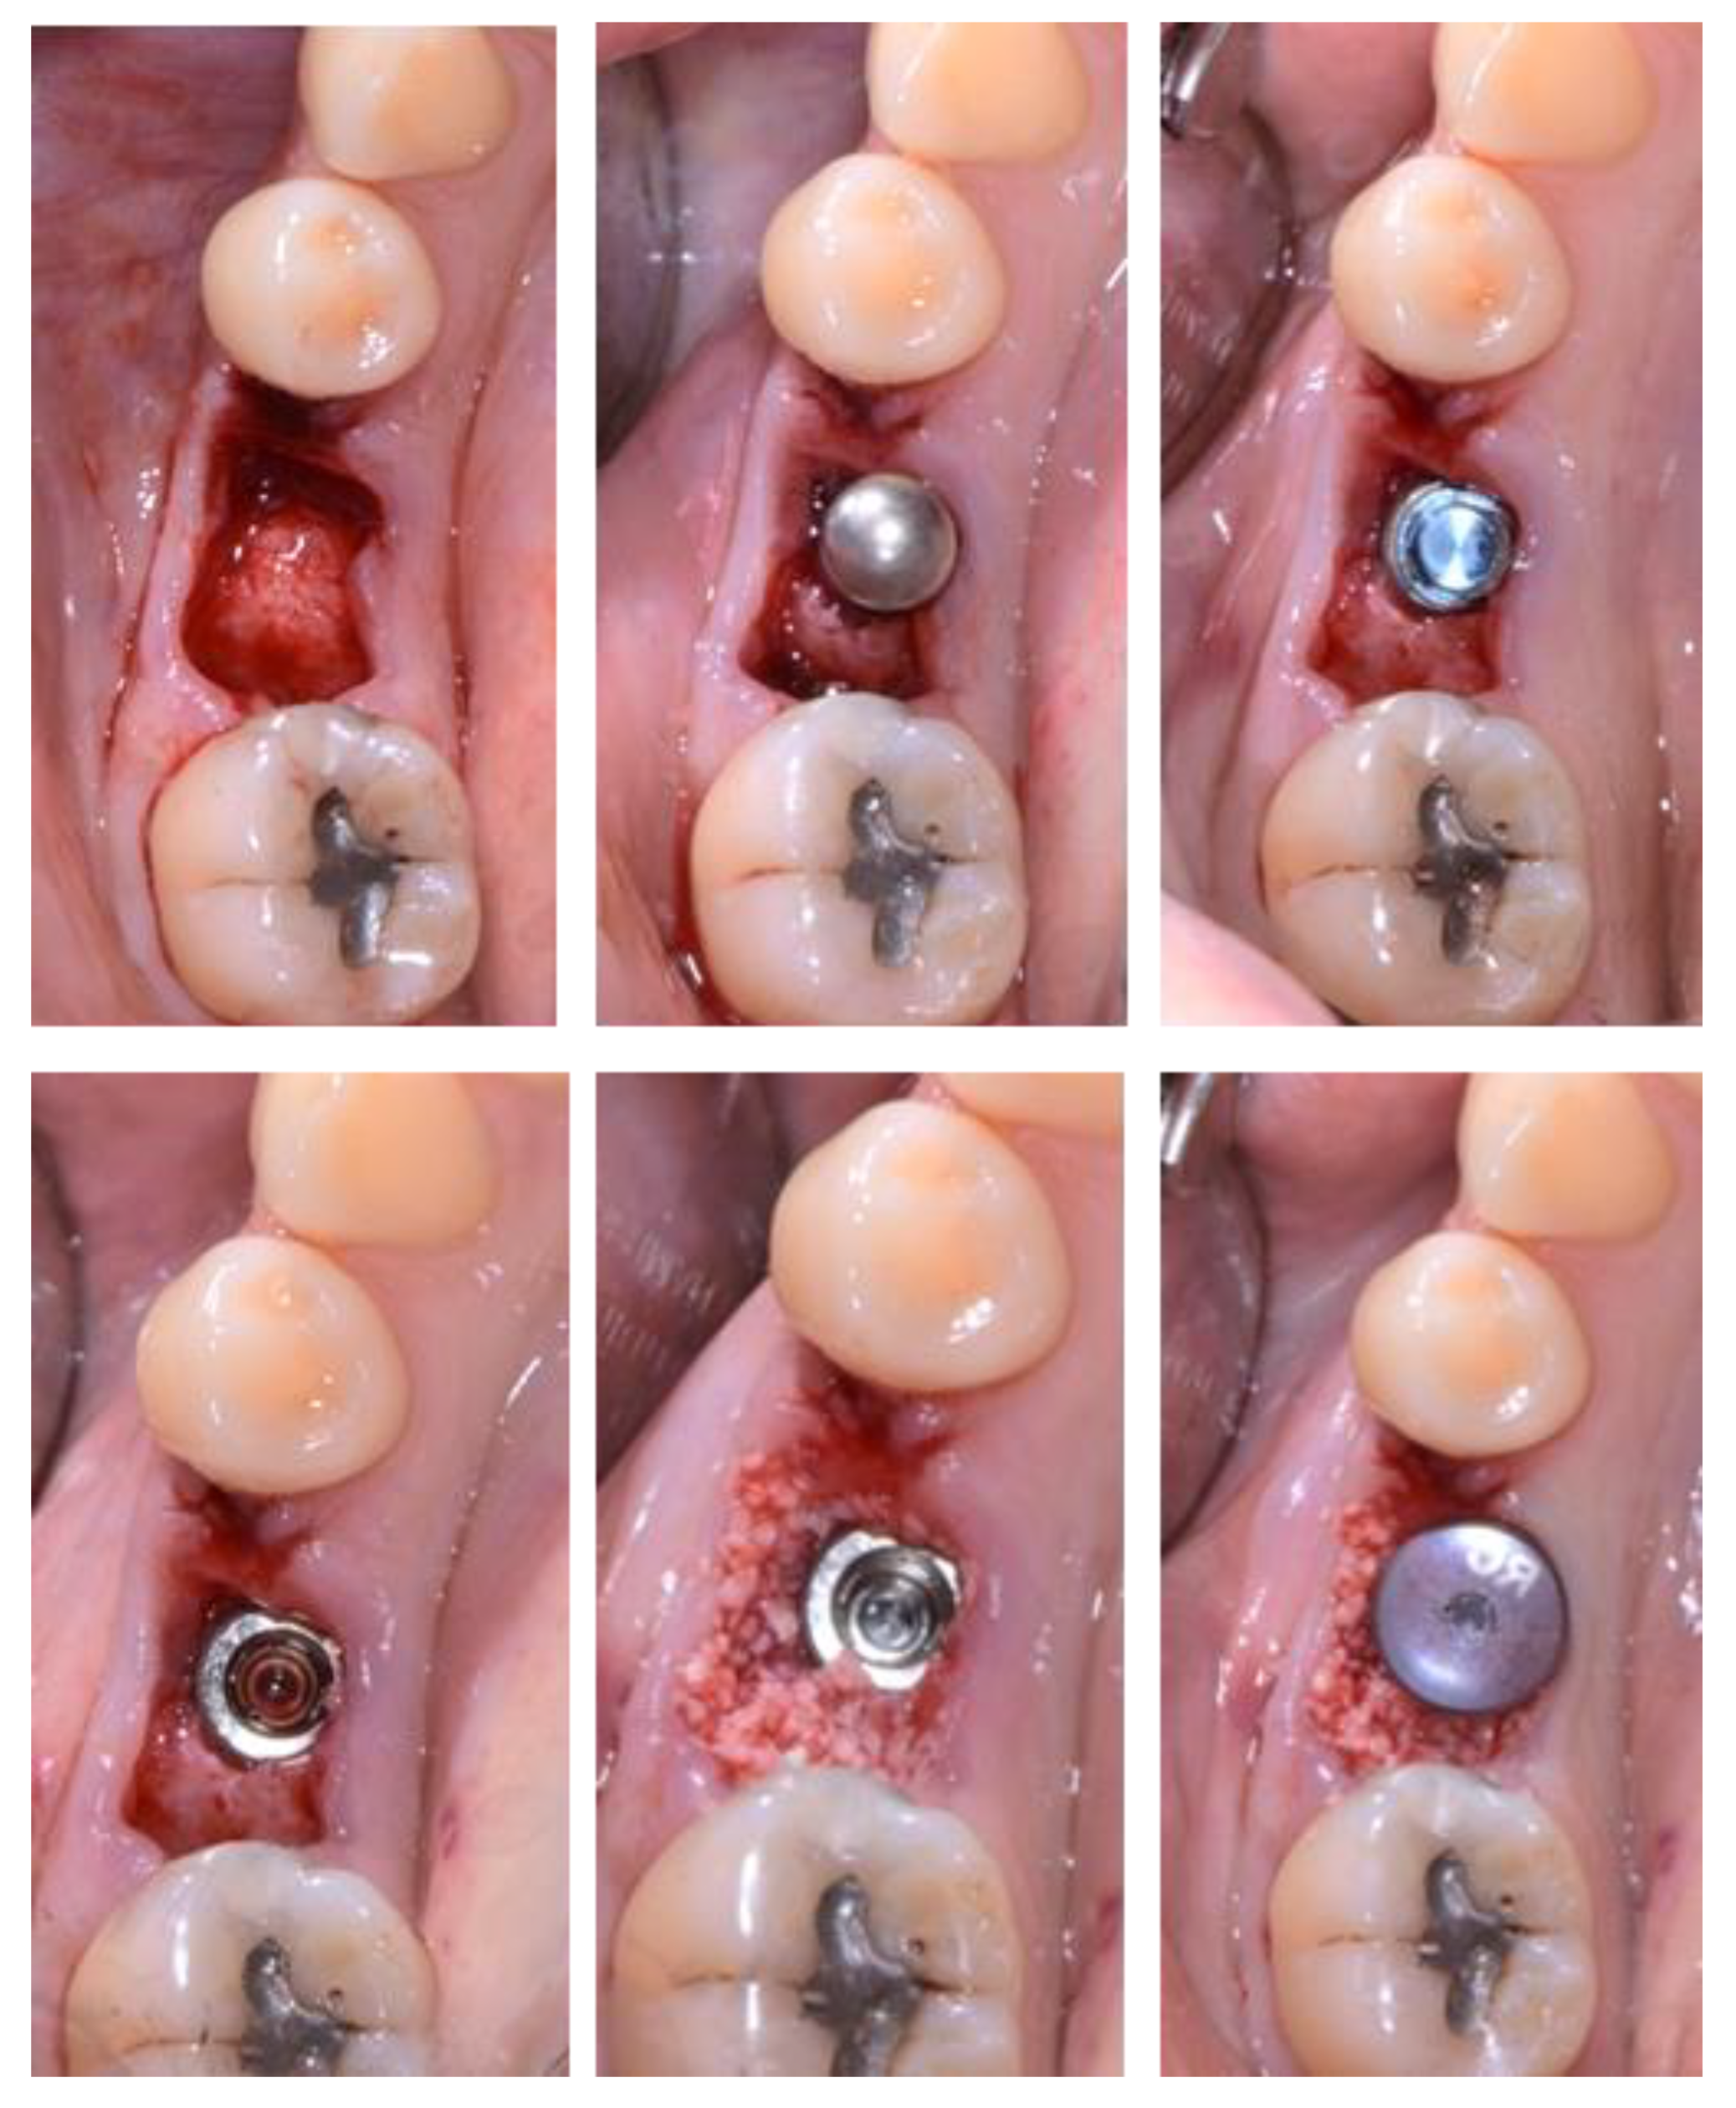

- Case 5: